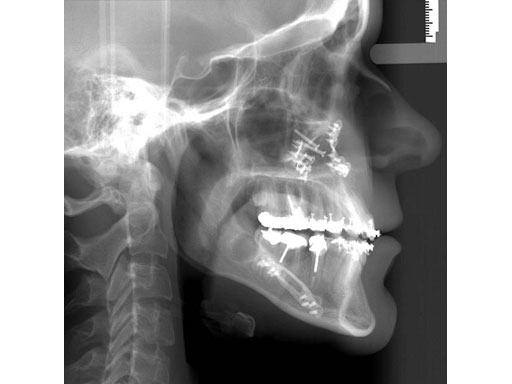

Lefort I maxillary osteotomy, bilateral sagittal osteotomies, and a genioplasty, all fixed with matrix orthognathic system used in a 19-year-old female with significant skeletofacial deformity including maxillary hypoplasia, mandibular excess, and laterognathia.

Fig 2a-c Postoperative images.